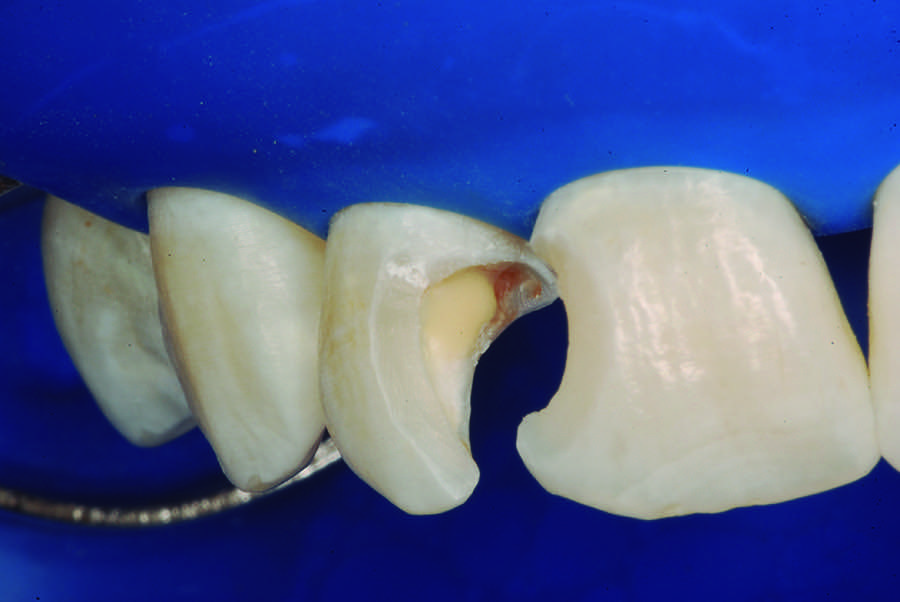

The partial pulpotomy was performed for tooth No. 7 due to the pulp exposure during the caries removal procedures (Figure 5). The superficial contaminated pulp tissue was removed with a No. 1012 spherical diamond bur at high speed with water cooling to allow a better reparative response. This procedure was limited to removal of the infected dentin and damaged pulp tissue, removing the injured odontoblast cell layer. During this step, the remaining pulp tissue was analyzed and found to have good consistency and abundant red bleeding (Figure 6). After the pulpotomy, a solution of calcium hydroxide was used for irrigation along with a sterile cotton pellet to achieve hemostasis and disinfection. After hemostasis, the tooth was treated with direct pulp capping: the exposed area was covered with calcium hydroxide powder (Figure 7) and calcium hydroxide cement (Figure 8). The cavity was provisionally restored with the use of a restorative GIC (Figure 9).

Fig 6. Aspect of the pulp after partial pulpotomy, showing the abundant red bleeding.

Figure 6